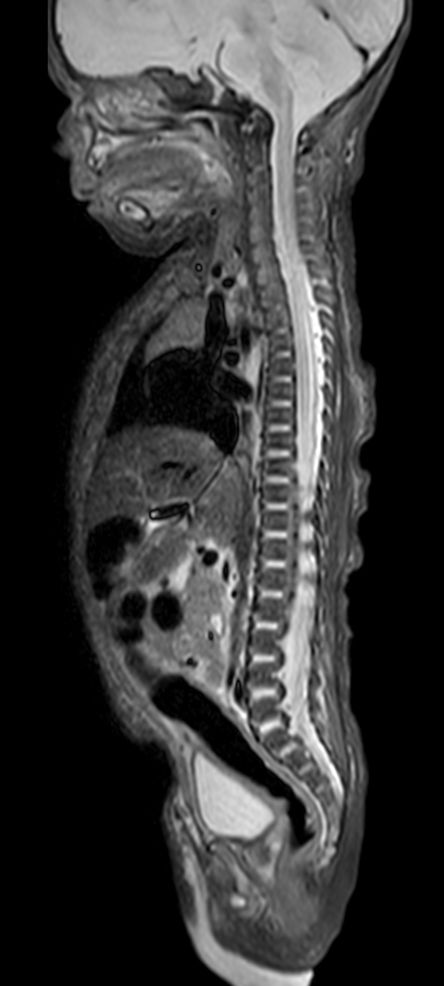

Pediatric Total Spine with spina bifida

Neonatal patient, 5 days old, with spina bifida